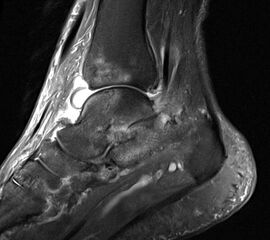

In der Frühphase einer Rheumaerkrankung können mit der MRT bereits Veränderungen an den Gelenken und Weichteilen identifiziert werden, die im konventionellen Röntgen nicht sichtbar sind.

Abbildung 5